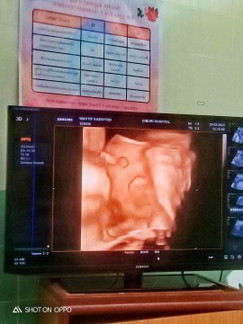

แม่ๆคนไหนพอจะรู้มั๊ยคะว่าปากน้องปกติดีรึป่าวพอดีมีคนบอกว่าน้องปากแหว่งค่ะ 😢

หมอที่รพ.บอกน้องปกติตอนนี้แม่บ้านนี้กังวลมากเลยค่ะ😞